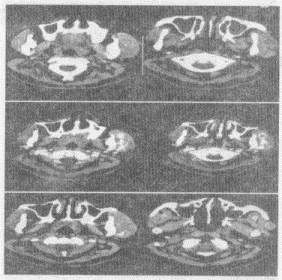

5.女,14歲,發現左側耳前腫大3個月余,PE:左頰部耳前彌漫性隆起,無壓痛,CT如圖所示,最可能的診斷是

正確答案:E